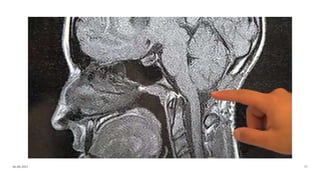

Aqueduct stenosis

Arnold-Chiari malformations

◦Portion of cerebellum and brainstem herniating into cervical spinal

canal, blocking the flow of CSF into the posterior fossa.